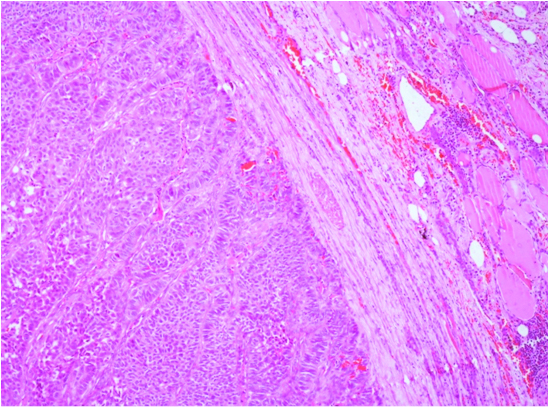

Patient underwent a left hemi thyroidectomy with frozen section followed by total thyroidectomy in the same sitting. The final histopathology, to our surprise, was reported as a single, well encapsulated, nodule measuring 3.5x3x2cm with neuro-endocrine differentiation. The macroscopically tan nodule displayed a trabecular pattern reminiscent of neuro-endocrine differentiation with invasion of vascular spaces [Table/Fig-2]. The immunohistochemistry profile revealed the tumour positive for CD56, synaptophysin, chromogranin and S-100 and negative for TTF-1, calcitonin and thyroglobulin [Table/Fig-3]. The Ki-67 proliferative index was >20% and with vascular invasion present making it grade 3. While the absence of both TTF-1 and thyroglobulin favored a non-thyroid origin, an interstitial pattern of infiltration with multiple nodules characteristic of thyroid metastases was conspicuously absent. The solitary nodule with a well delineated capsule favoured a primary thyroid tumour [Table/Fig-4]. The postoperative course was uneventful. The patient was referred back to the oncology department for chemotherapy.

Trabacular pattern in circumscribed nodule reminiscent of neuro-endocrine differentation with invasion of vascular spaces.

In an autopsy series the incidence of thyroid metastases in patients with known malignancy was 1.9-24%, the majority having lung, breast and melanoma as primary [6]. Metastatic tumours to the thyroid usually manifest as multiple tumour nodules infiltrating and undermining the thyroid parenchyma with multiple foci of vascular and lymphatic invasion [7]. In this case a circumscribed nodule invested by fibrous capsule was seen on H & E staining [Table/Fig-4], which was in favour of a primary and not metastases. On reviewing the literature, a second primary neuroendocrine tumour in a patient with a known primary, has not been described to the best of our knowledge. This highlights the dilemma we faced in diagnosing the patient since the clinical and histopathological findings did not correlate. Immunohistochemical studies are usually helpful in distinguishing metastatic disease from medullary carcinoma. Secondary neuroendocrine tumours of the thyroid usually are negative for calcitonin and Carcinoembryonic Antigen (CEA). However, calcitonin can be positive in cells of small cell carcinoma of the lung, but CEA is usually negative. The importance of history and physical examination in this setting is crucial as isolated metastasis to the thyroid is rare and patients usually have manifestations of metastasis to other organs. Besides, symptamology characteristic of neuroendocrine tumour such as diarrhea, flushing, weight loss may be elicited [8].